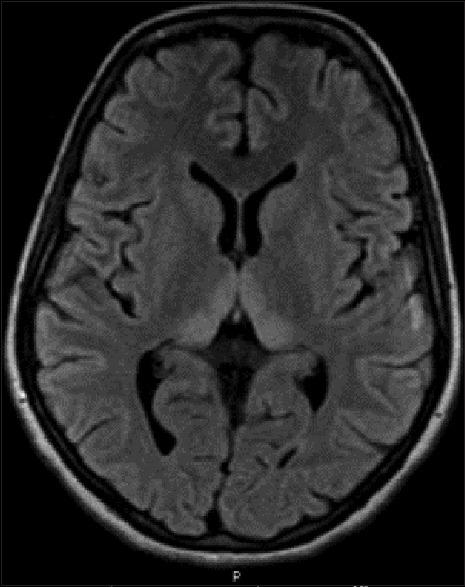

Hyperemesis gravidarum-induced Wernicke's encephalopathy (WE) is an underestimated condition. The purpose of this study is to improve its awareness and early diagnosis. We report five cases of WE secondary to hyperemesis gravidarum. Classic triad of encephalopathy, ataxia, and ocular signs was seen in four out of five patients. Two unusual features noted in this series were papilledema in one patient and severe sensory-motor peripheral neuropathy in one patient. Magnetic resonance imaging (MRI) was abnormal in all the five patients, and high signal in medial thalamus and surrounding the aqueduct was the most common abnormality (5/5). Involvement of caudate nucleus was seen in two patients with severe psychosis, and two patients had bilateral cerebellar peduncle involvement. Median time delay between onset of neurological symptoms and diagnosis was 7 days. All patients improved with thiamine, but minor sequelae were seen in four patients at 12 months follow-up. One patient had a fetal demise. Hyperemesis gravidarum-induced WE is a common cause of maternal morbidity. Typical MRI findings of symmetric medial thalamic and periaqueductal signal changes may permit a specific diagnosis. A delay in diagnosis, therefore treatment, leads to worse prognosis.

妊娠剧吐所致韦尼克脑病(WE)是一种被低估的疾病。本研究的目的是提高对其的认识并实现早期诊断。我们报告了5例继发于妊娠剧吐的韦尼克脑病病例。五分之四的患者出现了脑病、共济失调和眼部体征的典型三联征。本系列中注意到的两个不寻常特征是1例患者出现视乳头水肿,1例患者出现严重的感觉运动性周围神经病。所有5例患者的磁共振成像(MRI)均异常,内侧丘脑和导水管周围高信号是最常见的异常表现(5/5)。2例严重精神病患者出现尾状核受累,2例患者双侧小脑脚受累。神经症状出现至诊断的中位时间延迟为7天。所有患者经硫胺素治疗后均有改善,但在12个月的随访中,4例患者出现轻微后遗症。1例患者发生胎儿死亡。妊娠剧吐所致韦尼克脑病是孕产妇发病的常见原因。对称的内侧丘脑和导水管周围信号改变的典型MRI表现可能有助于做出明确诊断。诊断延迟进而导致治疗延迟会导致预后更差。